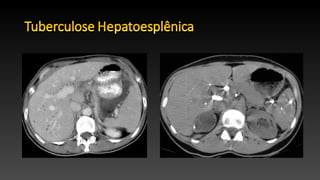

• Envolvimento hepatoesplénico é comum em pacientes com doença

disseminada e é ou micronodular-miliar ou macronodular.

• Envolvimento hepático miliar é observada em pacientes com

tuberculose pulmonar miliar e é caracterizada por inúmeros nódulos

0,5-2,0 mm, que não pode ser detectado na TC.

• Tuberculose hepática macronodular é incomum, e lesões são

hipoatenuantes na TC com margens mal definidas com realce

periférico.

• Envolvimento hepatoesplénicoé comum em pacientes com doença disseminada e é ou micronodular-miliar ou macronodular. • Envolvimento hepático miliar é observada em pacientes com tuberculose pulmonar miliar e é caracterizada por inúmeros nódulos 0,5-2,0 mm, que não pode ser detectado na TC. • Tuberculose hepática macronodular é incomum, e lesões são hipoatenuantes na TC com margens mal definidas com realce periférico.